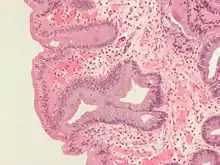

Micrograph of Barrett's esophagus, Alcian blue stain

Barrett's esophagus occurs due to chronic inflammation. The principal cause of the chronic inflammation is gastroesophageal reflux disease, GERD (UK: GORD). In this disease, acidic stomach, bile, and small intestine and pancreatic contents cause damage to the cells of the lower esophagus. Recently, bile acids were shown to be able to induce intestinal differentiation, in gastroesophageal junction cells, through inhibition of the epidermal growth factor receptor (EGFR) and the protein kinase enzyme Akt.[11]

Both macroscopic (from endoscopy) and microscopic positive findings are required to make a diagnosis. Barrett's esophagus is marked by the presence of columnar epithelia in the lower esophagus, replacing the normal squamous cell epitheliuman example of metaplasia. The secretory columnar epithelium may be more able to withstand the erosive action of the gastric secretions; however, this metaplasia confers an increased risk of adenocarcinoma.[15]